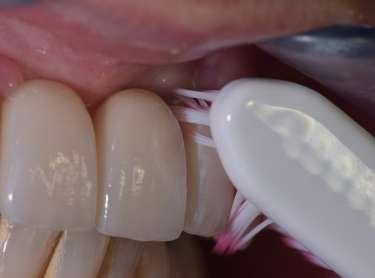

Le innovazioni tecnologiche per l’efficace mantenimento delle riabilitazioni implantari

La prevenzione terziaria è una vera sfida per l’igienista dentale, che per competenza del suo profilo professionale ha la gestione del mantenimento delle riabilitazioni odontoiatriche.

Le terapie riabilitative implantari per pazienti con edentulia parziale o totale, permettono di riportare sia la funzionalità che l’estetica, con una prevedibilità di successo che dipende, oltre che dall’efficace piano terapeutico chirurgico implantare del professionista chirurgo, anche dalla responsabilità attiva del paziente a seguire corretti stili di vita di igiene orale domiciliare e follow-up. Questi devono prevedere la visita diagnostica di controllo dell’implantologo e la visita di controllo dell’igienista dentale. Per sollecitare l’aderence ai follow-up, usare l'automazione workflow e moduli di anamnesi personalizzati (gestionale Alfa Docs) permette una migliore gestione e un monitoraggio efficace delle cure e dei richiami personalizzati in base ai bisogni extra clinici dei pazienti. La vera sfida è il management di igiene orale in pazienti presi in carico che sono stati sottoposti a terapie implantari in altri studi, e che mostrano clinicamente mucosite, con interessamento della mucosa perimplantare o con perimplantite che coinvolge l’osso di sostegno.

Spesso si evidenzia il collare implantare degli abutment, e prima che l’implantologo preveda intervento mucogengivale è fondamentale condividere con il paziente la necessità di eliminare l’infiammazione eseguendo un'igiene orale domiciliare attenta ed efficace. L'igiene orale domiciliare deve essere considerata terapia.

biofilm batterico domiciliare. Per il controllo meccanico del biofilm batterico, se viene lamentata dolorabilità, si deve concordare l'uso di uno spazzolino con setole che siano efficaci ma che non creino dolorabilità durante l’utilizzo (GUM Sonic Sensitive).

L’utilizzo degli scovolini in gomma, (GUM Soft Picks Confort Flex), risultano essere delicati sui tessuti perimplantari, ed efficaci, grazie alle differenti misure possibili, per la personalizzazione della scelta dell’interprossimale a seconda dello spazio sovracrestale.

(TBM) Nardi G.M. et al. Tailored Brushing Method (TBM): an innovative simple protocol to improve the oral care. J Biomed 2016; 1:26-31. Il protocollo di igiene orale deve essere personalizzato in base alla tipologia del manufatto protesico implantare, poiché spesso la persona assistita ha difficoltà di efficacia nel controllo del

Per il controllo chimico del biofilm batterico domiciliare, l’olio di oliva ozonizzato è molto apprezzato dalla persona assistita poiché ha un gusto gradevole, non crea discromie sulle superfici dentali e implantari e può essere usato quotidianamente, aspetti che non vanno trascurati poiché permettono compliance e maggiore aderence alle terapie di igiene orale domiciliare.

L’uso del colluttorio all’olio di oliva ozonizzato Ialozon Blu (GEMAVIP),